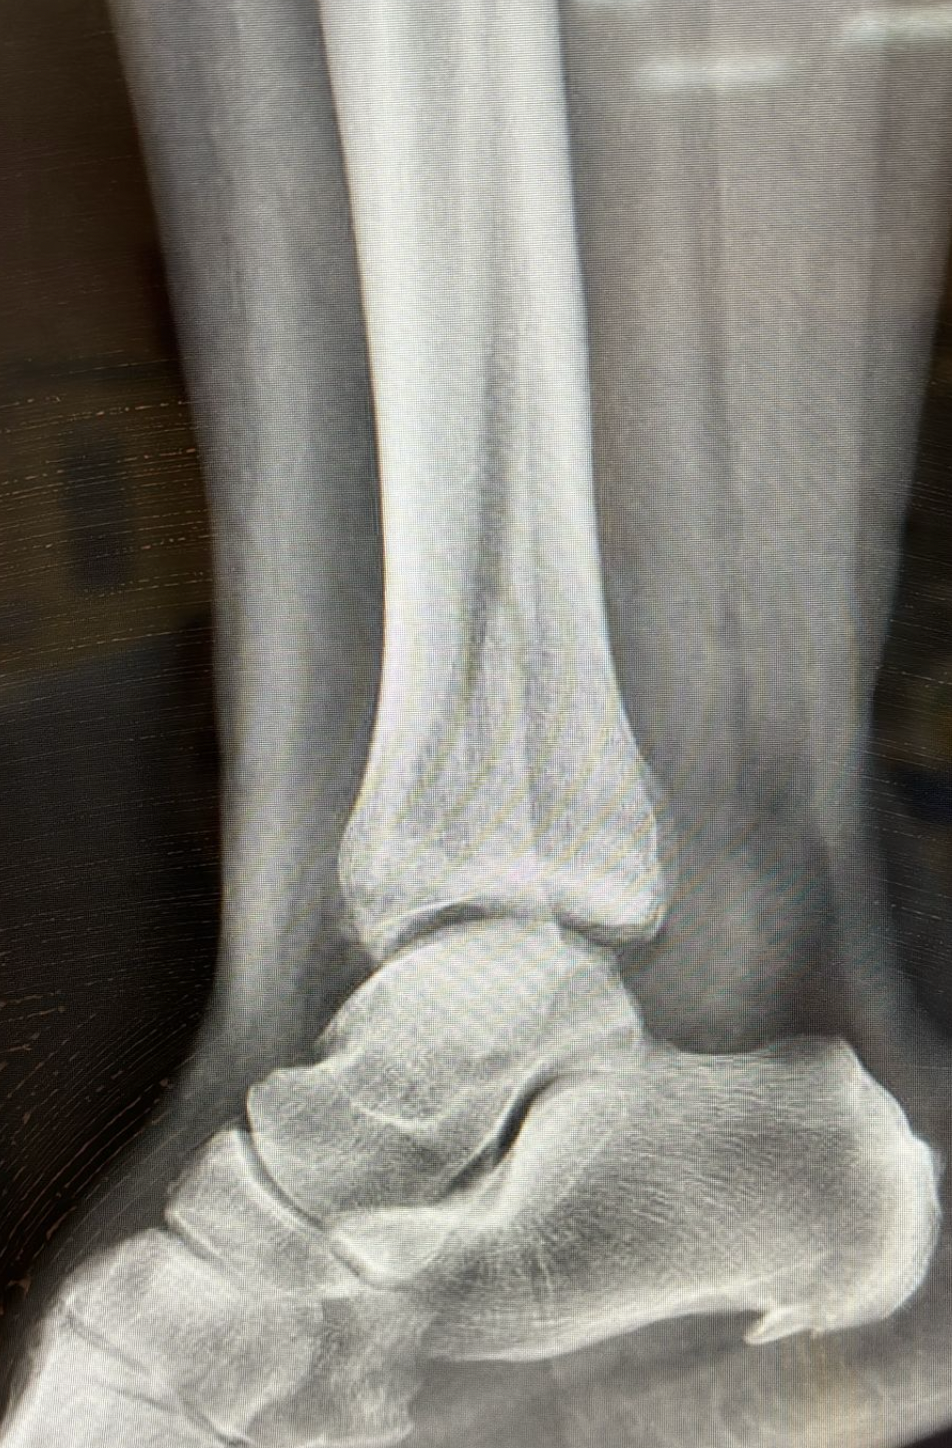

It is not always easy to determine whether ankle pain is caused by a sprain or a fracture. For this reason, it is advisable to visit an emergency room and undergo an X-ray.

- After 60 days, the cast is removed, X-rays are performed, and a walker boot is provided. Rehabilitation begins, with gradual weight-bearing of about 50 kg for another 30 days.